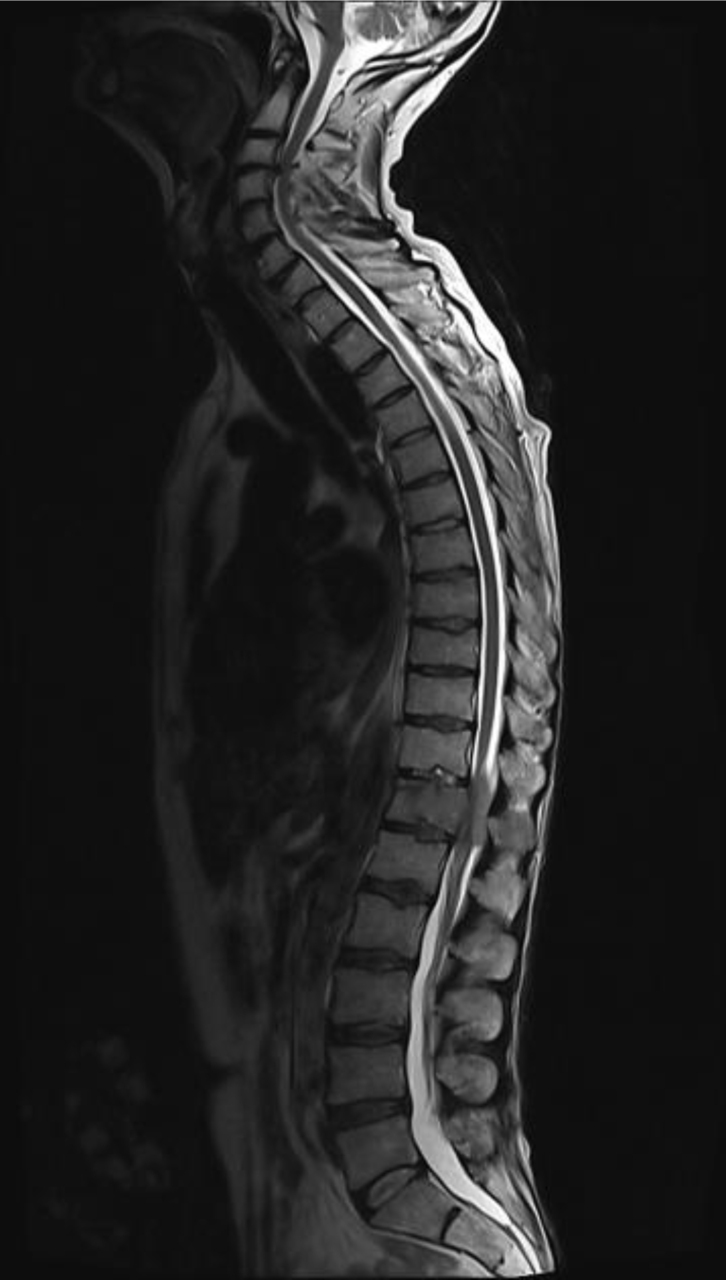

Vous êtes en attente des résultats de la biopsie sus-claviculaire gauche, dont vous avez seulement eu des résultats partiels, qui confirment la présence de cellules tumorales. Alors qu’elle est toujours hospitalisée, la patiente a un épisode de crise tonicoclonique généralisée, spontanément résolutive en 1 minute, avec retour à un état de vigilance satisfaisant. Vous faites réaliser en urgence l’examen suivant (fig. 2) :

Figure 2 (source : M. Roulleaux Dugage)

Question 4 - Concernant cet examen, il vous semble que :

Pour rappel, il s’agit d’une séquence T1 (car anatomique : la substance blanche est plus claire que la substance grise) avec injection de gadolinium (prise de contraste des sillons et des artères méningées). C’est une image typique de métastase cérébrale avec une image arrondie, sous-corticale, avec œdème périlésionnel (hyposignal T1), avec l’image en cocarde (prise de contraste périphérique).

Vous avez introduit un traitement de fond antiépileptique par lévétiracétam. La patiente était déjà sous corticoïdes pour la compression médullaire. Pour les neurochirurgiens, il existe l’indication d’une irradiation stéréotaxique, mais sans urgence (pas d’hypertension intracrânienne [HTIC] ni de déficit sensitivomoteur). Vous êtes en attente des résultats de la biopsie sus-claviculaire, que vous aurez plus tard dans la journée. La radiothérapie de T11-T12-L1 débutera le lendemain. Vous discutez avec un confrère du dossier et du type tumoral le plus probable devant les éléments dont vous disposez.